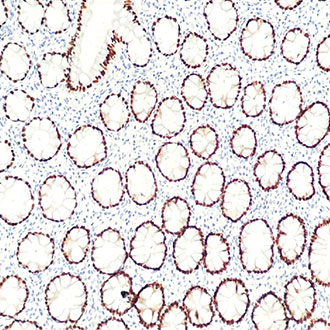

IHC

免疫组织化学(IHC)